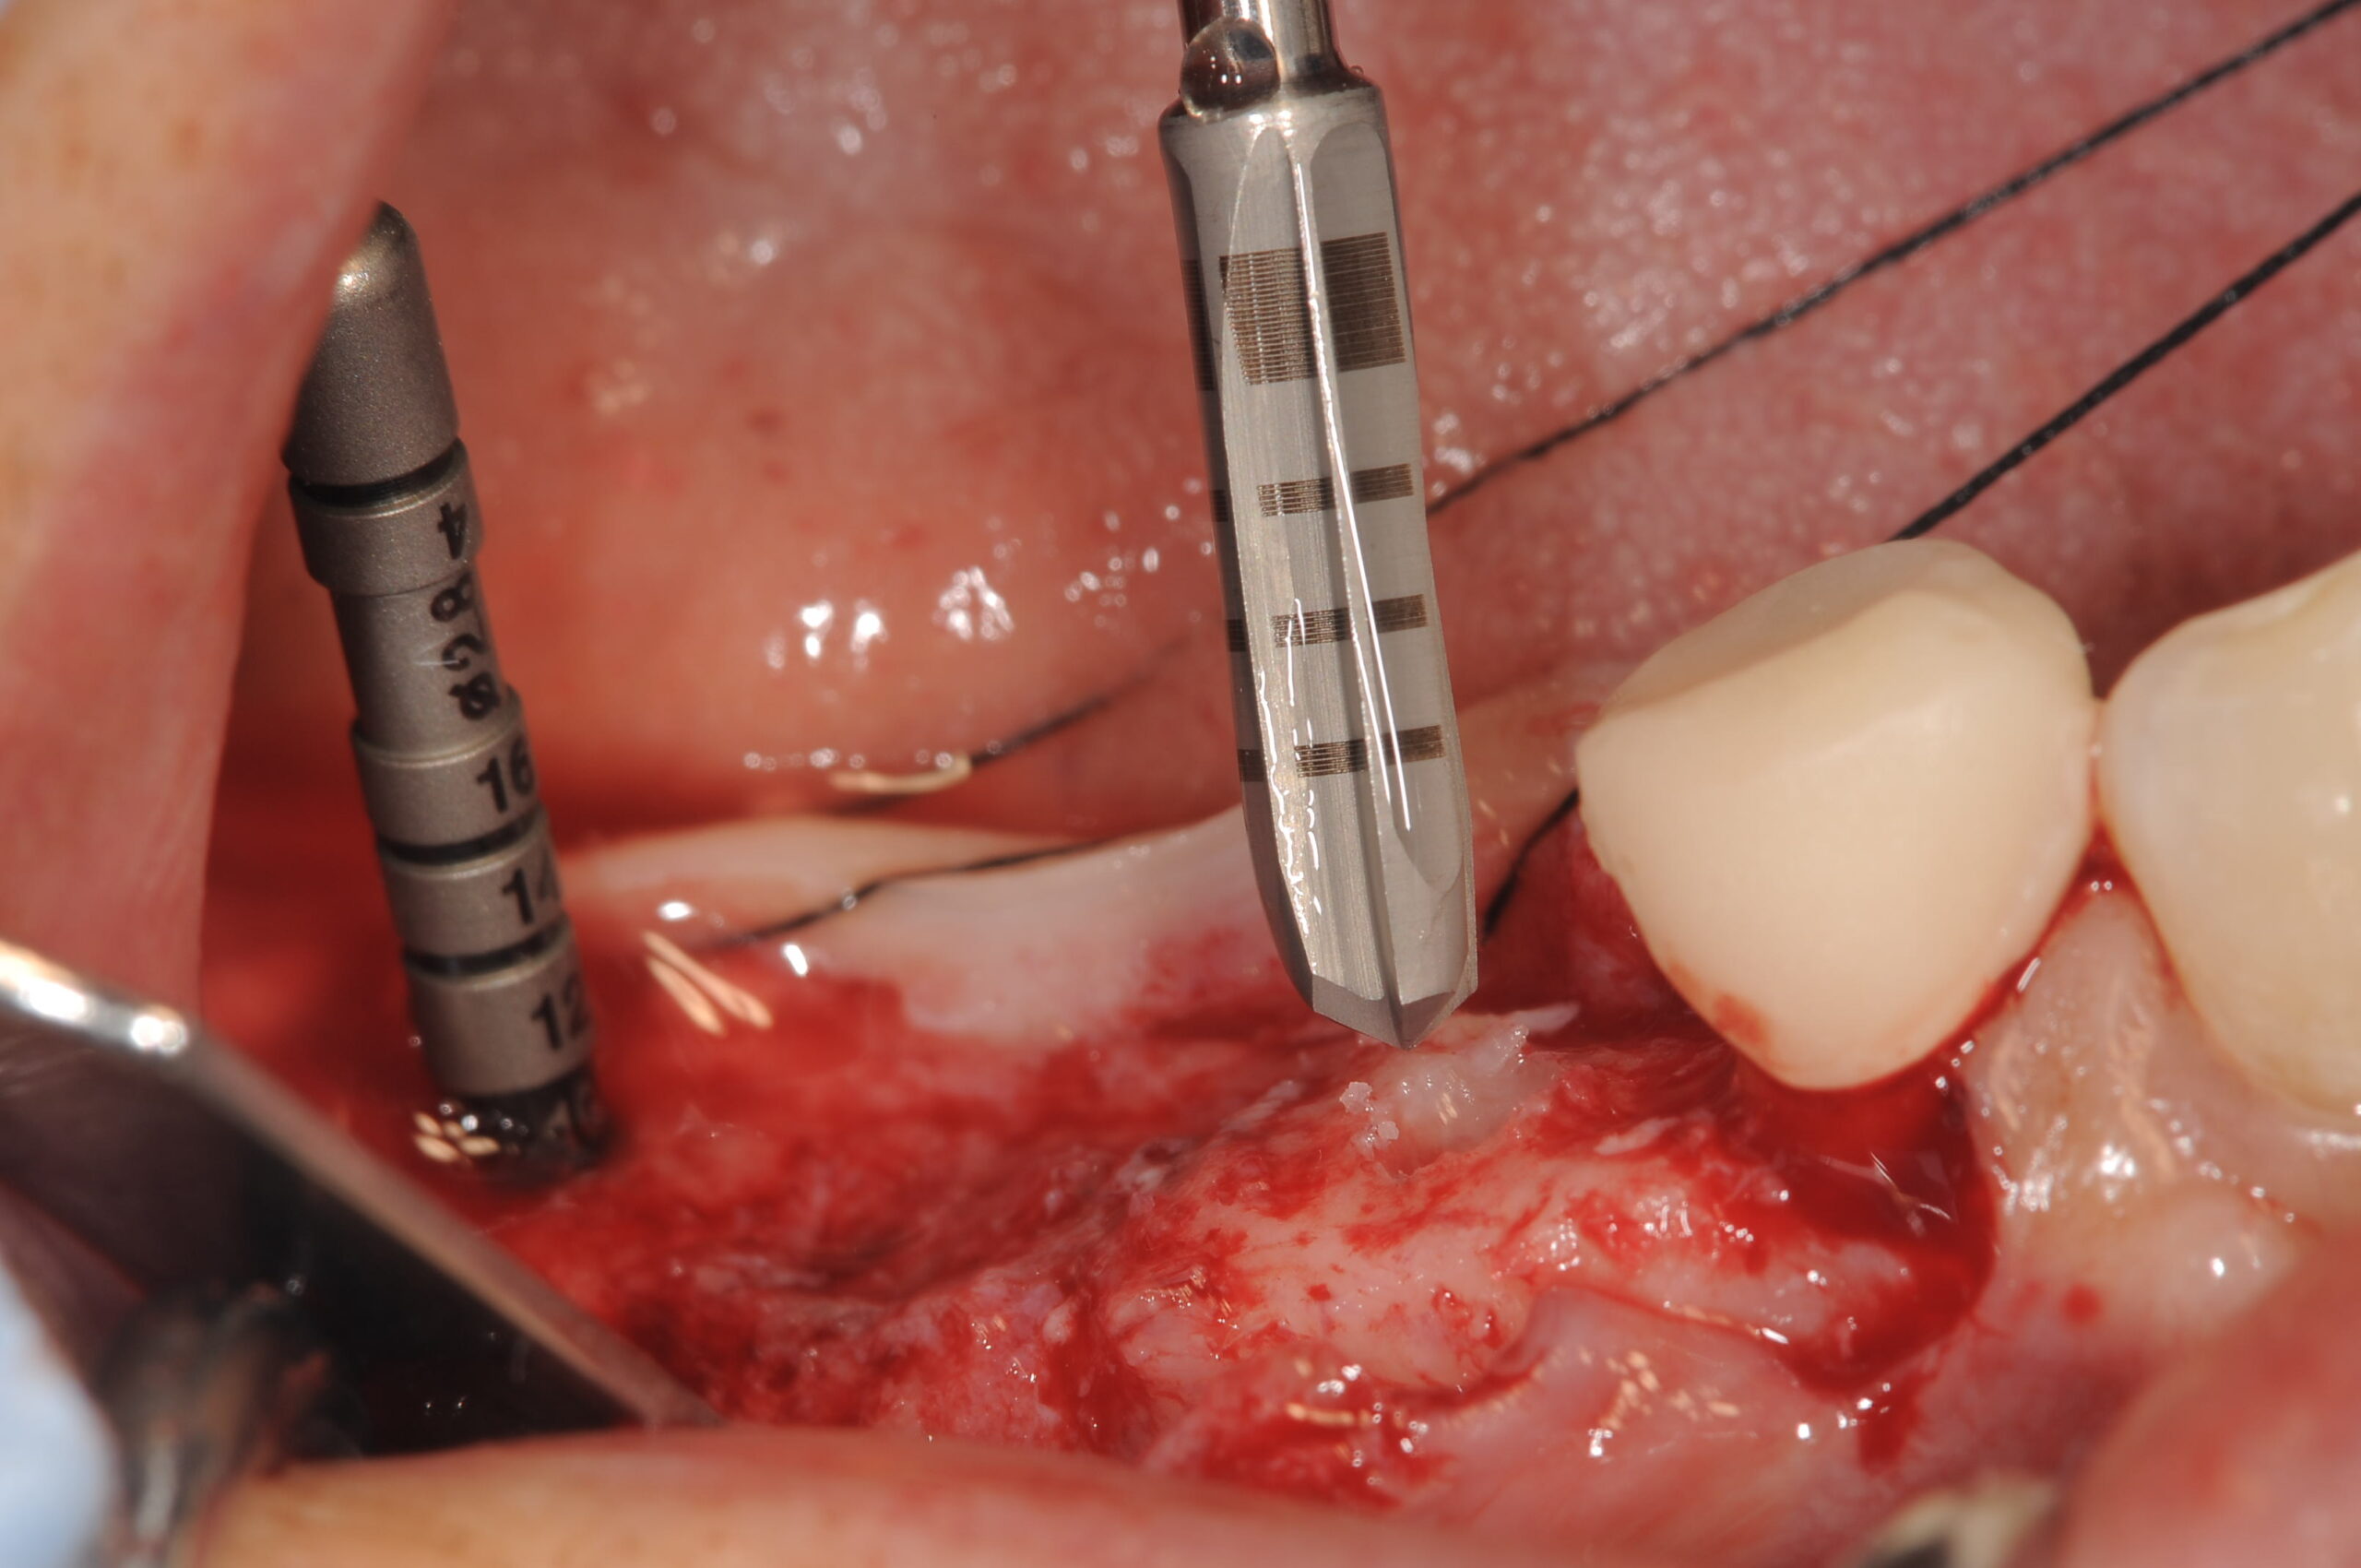

埋入部位をフラットにした上で、ドリリングしていきますが、ドリルにもテーパーがついていますので、非常にスムーズに形成できます。

使用したBLT(Bone Level Tapered)のSLActiveです。